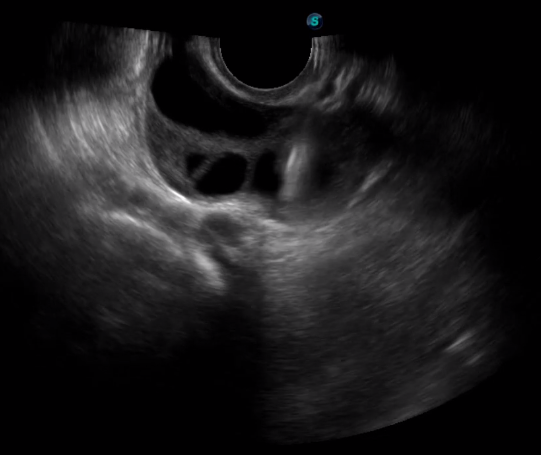

TEE(經(jīng)食道超聲心動圖)將超聲探頭置入食道內,從心臟的后方向前近距離探查其結構 ,克服了經(jīng)胸超聲檢查的局限性,避免肺內氣體、胸壁脂肪、胸廓畸形等因素影響,觀察角度更多,圖像更加清晰,測量數(shù)據(jù)更準確。

經(jīng)食道超聲 大動脈短軸